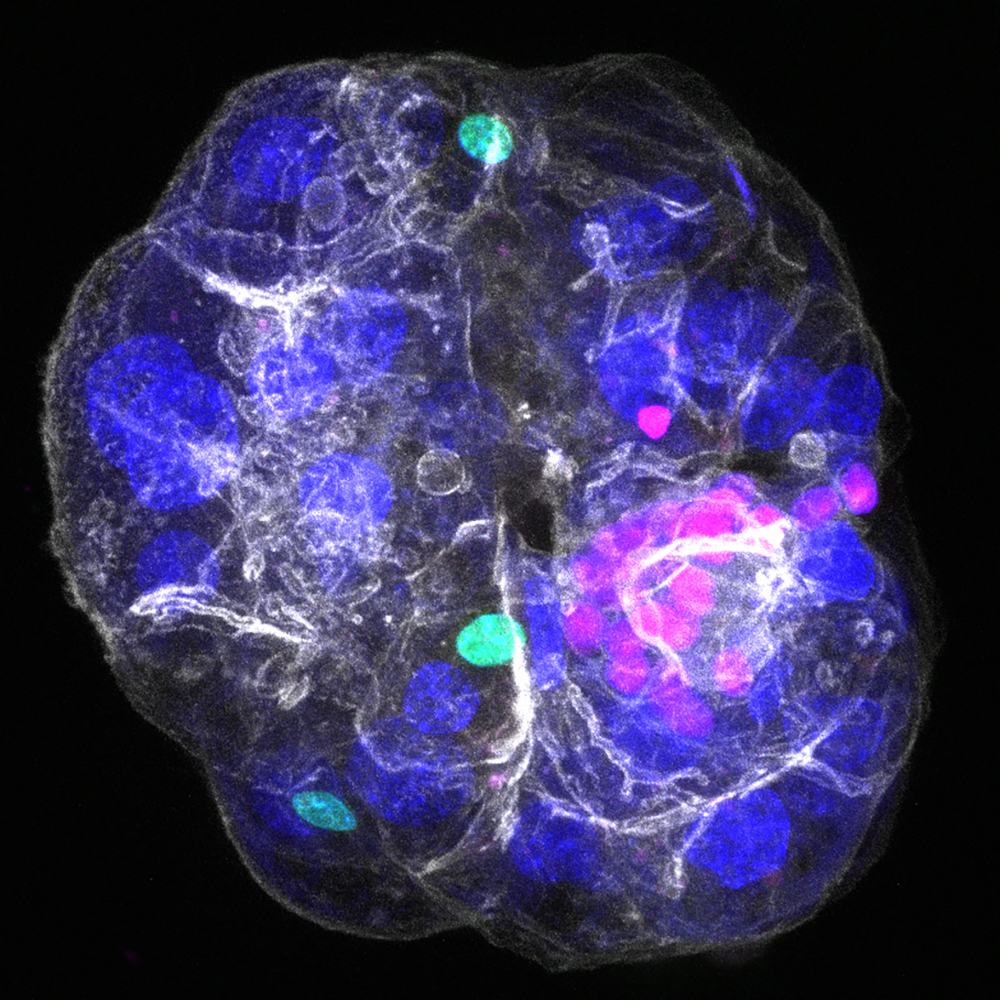

In this current study, published in the journal Nature, researchers from the group of Meritxell Huch, together with colleagues from the groups of Marino Zerial and Heather Harrington, both also directors at the MPI-CBG, were able to develop a next-generation organoid model, which they named “periportal assembloid.” This assembloid features adult cholangiocytes and liver mesenchymal cells (as in the previous model), but now additionally also includes hepatocytes, which are the main functional cells of the adult liver. This model combines different cells assembled together in a stepwise process one could compare to LEGO.

“To achieve our goal, we first created organoids only consisting of hepatocytes that formed working bile channels and maintained key features of real hepatocytes in the tissue. Then, we added cholangiocytes and fibroblast cells to build periportal assembloids. Our liver model works like real liver tissue, moving bile from inside the liver cells into bile ducts, which shows that we were able to replicate the interactions between the different liver cells,” explains Aleksandra Sljukic, also first author of the study and a doctoral student in the Huch group.

Meritxell Huch, who oversaw and supervised the study, concludes, “We are excited that we were able to create a periportal assembloid model that combines, for the first time, portal mesenchyme, cholangiocytes, and hepatocytes. Although some cells are still missing, namely the endothelium and immune cells, the model captures with high precision the cellular and structural architecture of the liver's periportal area at the scale of a tissue culture dish. Additionally, its modular features allow it to be easily studied, handled, and manipulated in the lab. Our liver assembloids are the first all-in-one lab model that can be used to study bile flow, bile duct injury, and how different liver cells contribute to disease.”